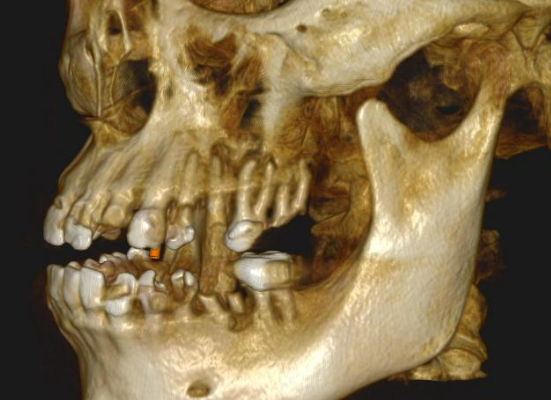

Long-term psychoactive substance use had caused severe xerostomia, contributing to the rapid development of dental caries and decay. The teeth in the upper jaw were non-restorable, and many were already missing. The condition of the lower jaw was slightly better: the anterior teeth were in satisfactory condition, but the posterior teeth were severely decayed and required extraction.

The presented images show the patient’s initial dental condition.

The implants were placed immediately following tooth extraction. They were positioned subcrestally — 2–3 mm below the bone crest — to allow for anticipated bone remodeling. A total of eight implants were placed in the maxilla and four in the mandible.

Placing the implants into the fresh extraction sockets allowed for optimal positioning for the future prosthetic restoration. The extractions were performed using the root shield technique, which is aimed at maintaining the thickness and height of the buccal and palatal bone walls. This technique, traditionally used for “conservation” even in case of delayed implantation, helps to minimize resorption and preserve the natural morphology of the alveolar ridge.